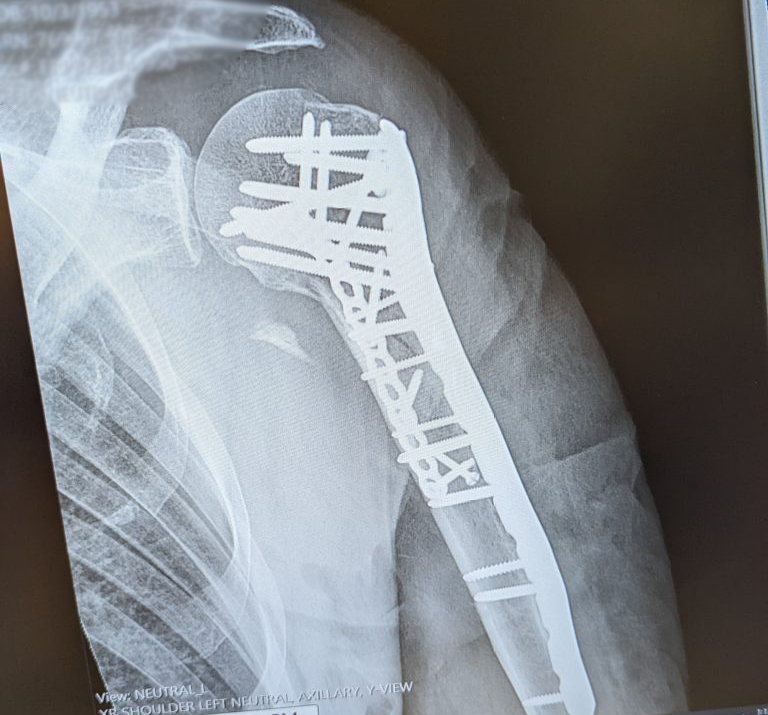

Fast forward to 2023. A serious fall at home shattered my left proximal humerus (upper arm and shoulder). This was a traumatic injury that required immediate intervention. After going to my local ED to have the arm x-rayed and put in a sling, I called Dr. John Lyden at HSS, the surgeon who had replaced my right hip in 2017. He saw me immediately, and after consultation, referred me to the surgeon who would repair my shattered shoulder, Aleksey Dvorzhinskiy.

Dr. Dvorzhinskiy, who was available immediately by cell phone, spent several calls with me discussing the pros and cons of surgery, and the possible outcomes for my recovery of function with and without surgery. I opted for the surgery. After a seven-hour surgery including multiple screws and two plates, I was in recovery and slowly waking up. I spent several days at HSS, receiving the responsive, skilled care I knew to expect.